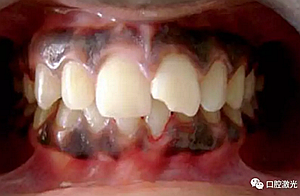

術(shù)后一周

術(shù)后三月